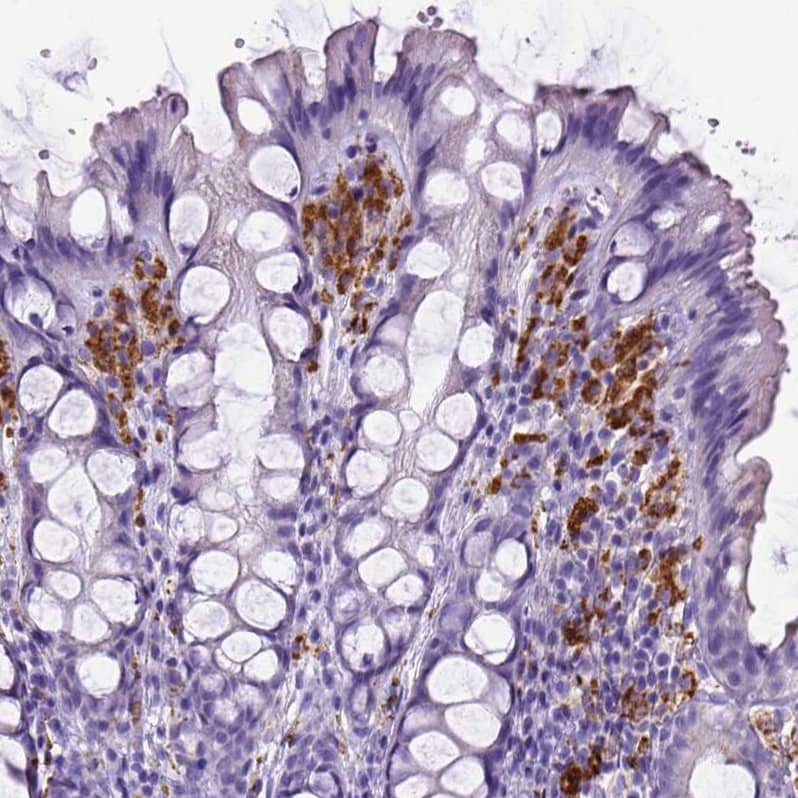

Staining of human colon shows strong cytoplasmic positivity in lymphoid cells.